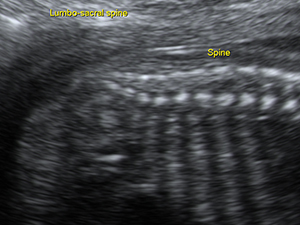

脊椎

中孕期的胎兒脊骨